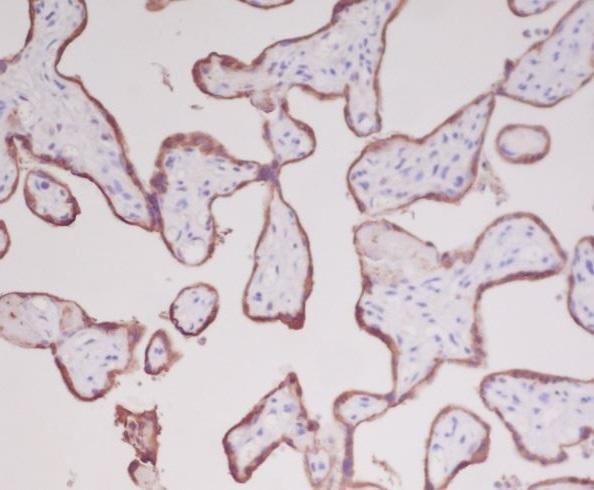

分类: 科研抗体货号: P17569别名: Cas1; CAT; Catalase; Cs1;;Catalase应用: WB;IHC反应种属: Human,Mouse,Rat